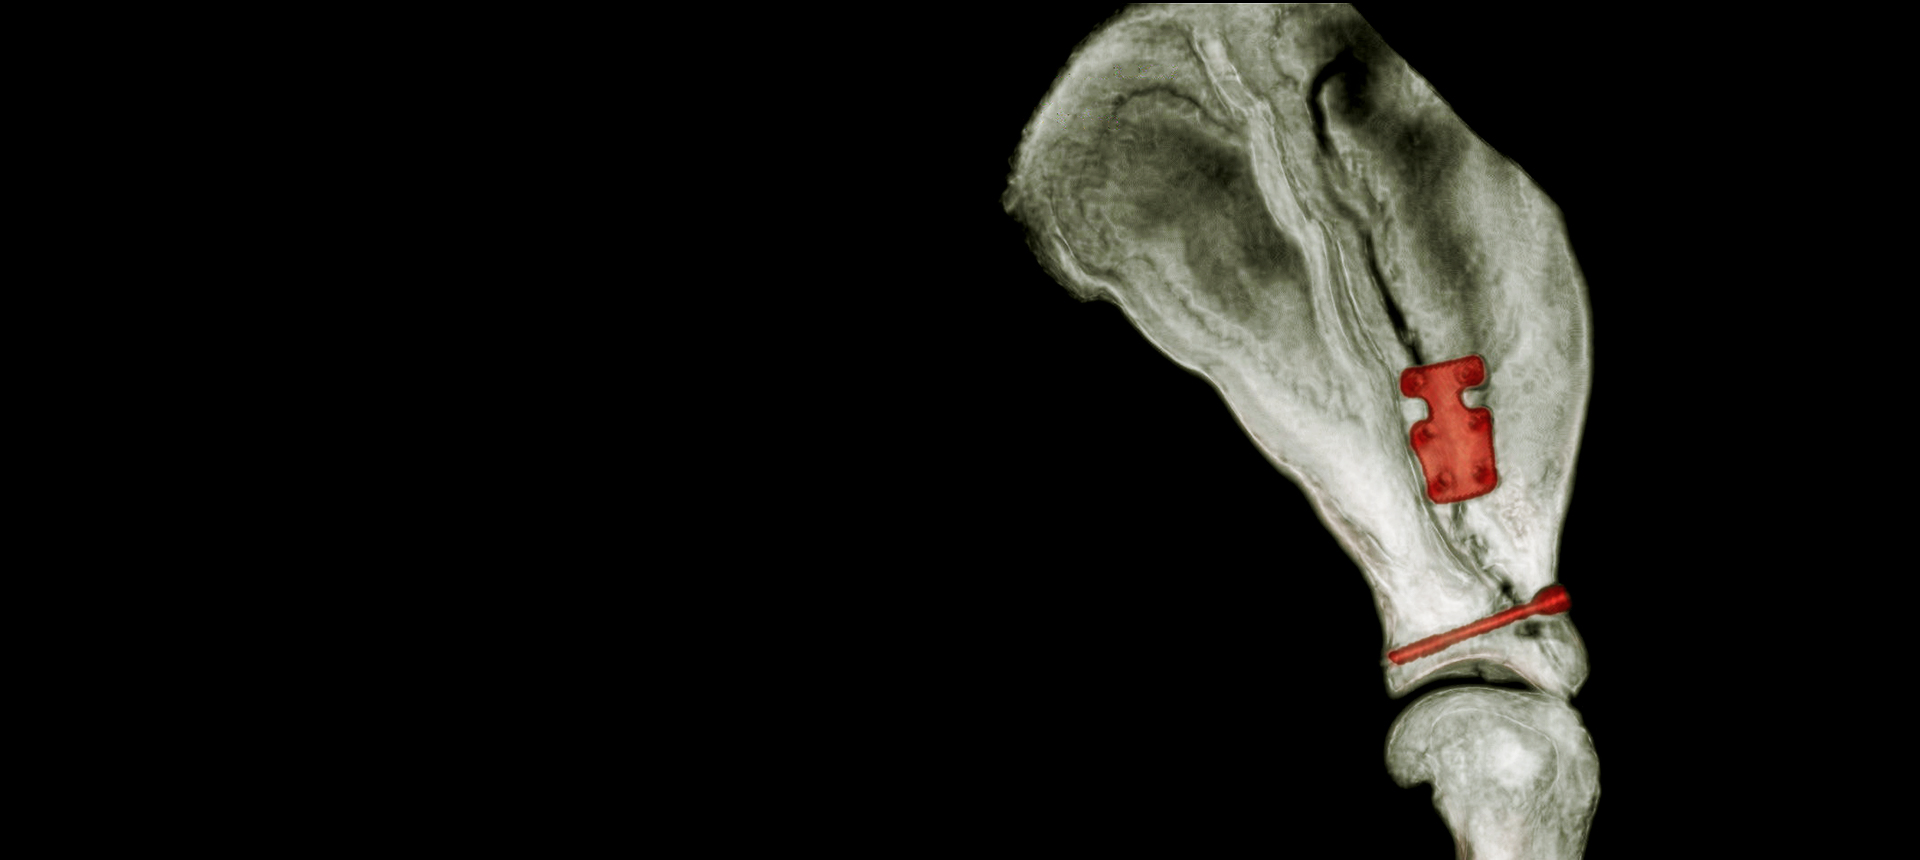

Pioneering Small PatientOrthopedics with the 1.5 mmLeiLOX TPLO Swing Titanium Plate ...